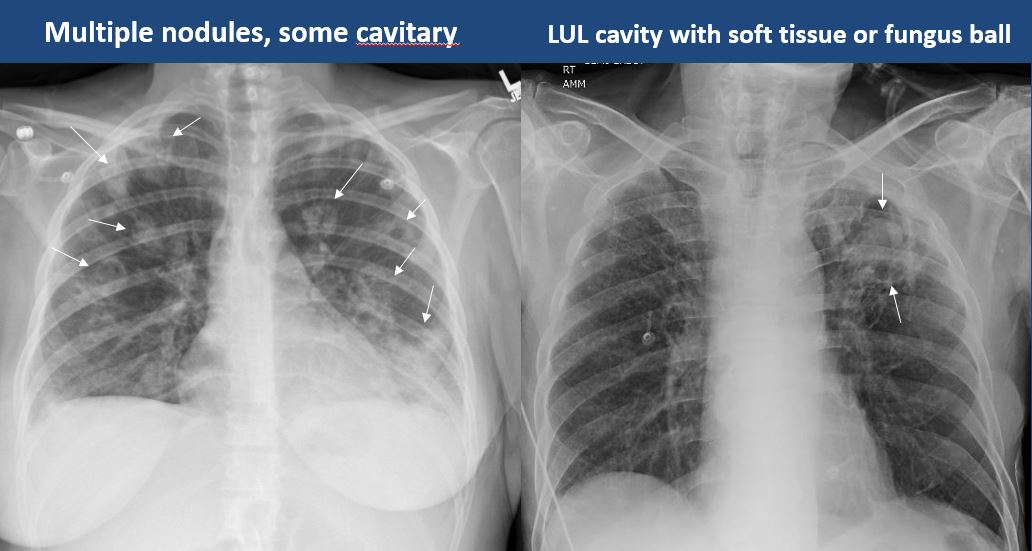

There is cavitary or cystic disease with or without air fluid levels or soft tissue nodularity. [Yes/No]